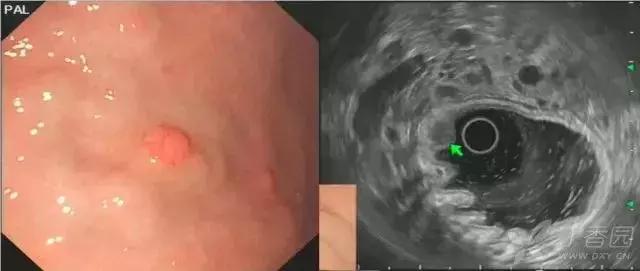

图 1 A-B 胃体上后壁间质瘤;D-E 胃窦前壁间质瘤,以上病变均起源于黏膜第四层,与周围黏膜界线清晰,与肌层延续处可观察到「喇叭口」样结构(箭头所示)